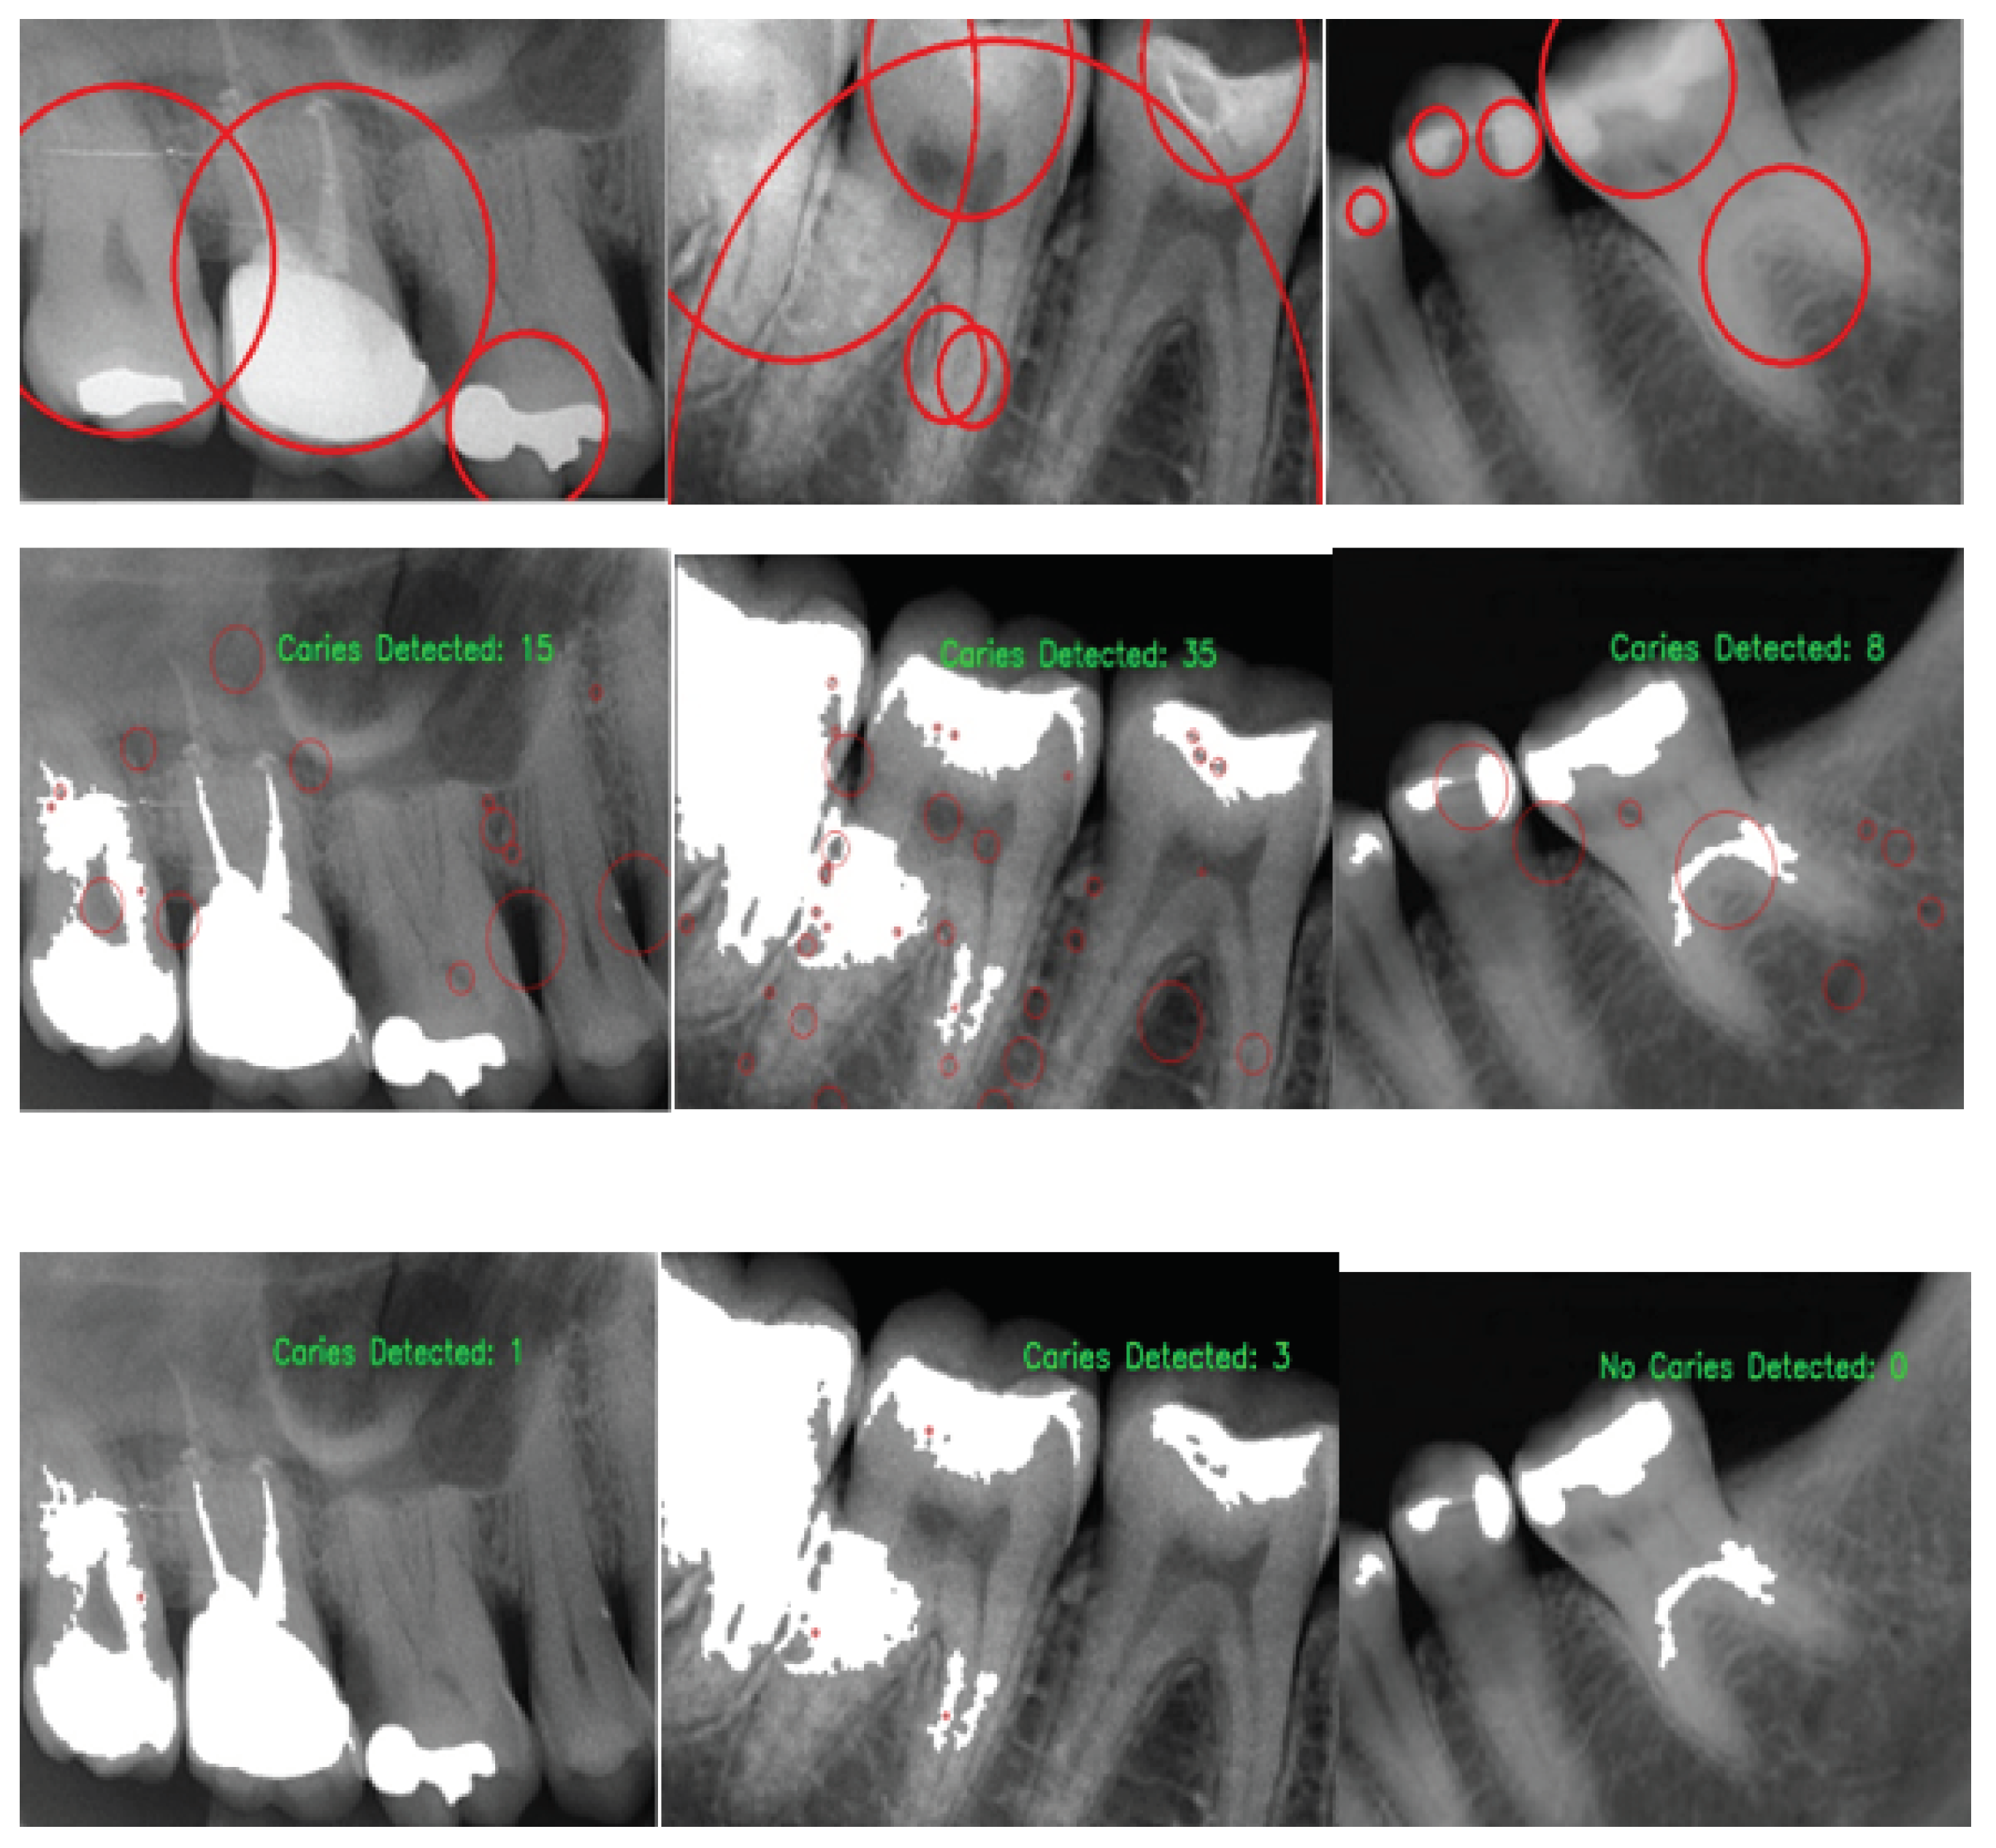

2.3.2. Caries Candidate Detection

2.3.3. Caries Candidate Selection

3. Results and Discussion